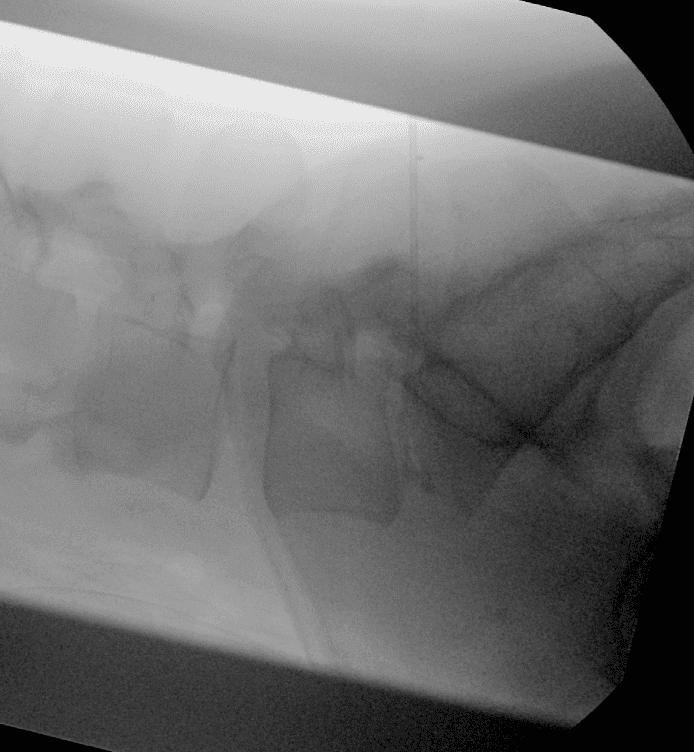

Insertion percutanée sous guidage

Sous anesthésie locale (parfois combinée à une légère sédation), une aiguille fine est introduite de manière percutanée dans le disque intervertébral.

Le guidage en temps réel par fluoroscopie ou scanner assure une précision optimale, minimisant ainsi le risque de lésion des structures adjacentes.